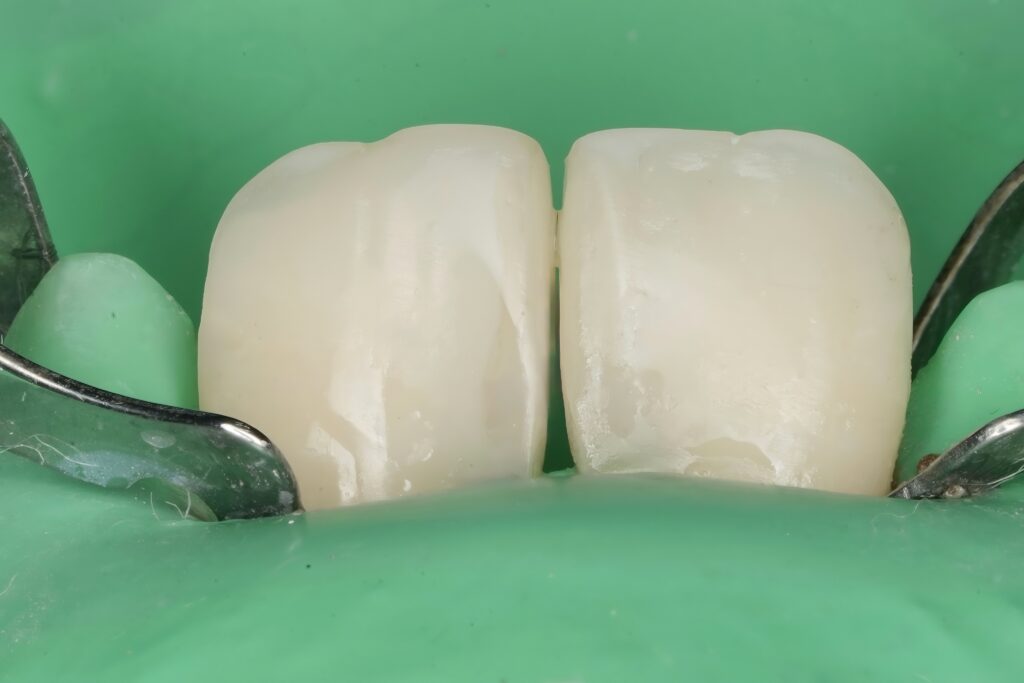

Step 6 – Finishing and Polishing

- Interproximal refinement for smooth contact

- Line angle definition for optical narrowing

- Multi-step polishing system to achieve enamel-like gloss

Surface texture was reproduced to mimic natural enamel light reflection.

Step 5 – Composite Layering Technique

A biomimetic layering approach was used:

- Palatal shell first to establish framework

- Dentin body shade to create opacity

- Enamel layer for translucency

- Subtle characterization for depth

Each increment was sculpted anatomically rather than bulk-filled, restoring natural line angles and surface morphology.